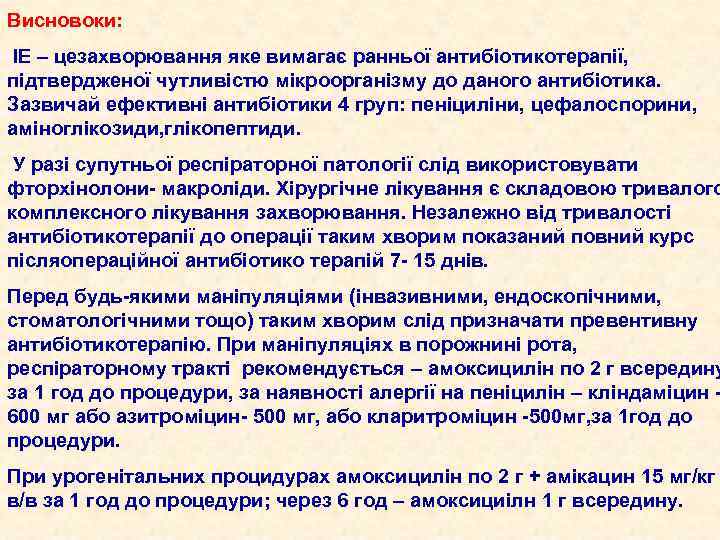

Висновоки: ІЕ – цезахворювання яке вимагає ранньої антибіотикотерапії, підтвердженої чутливістю мікроорганізму до даного антибіотика. Зазвичай ефективні антибіотики 4 груп: пеніциліни, цефалоспорини, аміноглікозиди, глікопептиди. У разі супутньої респіраторної патології слід використовувати фторхінолони- макроліди. Хірургічне лікування є складовою тривалого комплексного лікування захворювання. Незалежно від тривалості антибіотикотерапії до операції таким хворим показаний повний курс післяопераційної антибіотико терапій 7 - 15 днів. Перед будь-якими маніпуляціями (інвазивними, ендоскопічними, стоматологічними тощо) таким хворим слід призначати превентивну антибіотикотерапію. При маніпуляціях в порожнині рота, респіраторному тракті рекомендується – амоксицилін по 2 г всередину за 1 год до процедури, за наявності алергії на пеніцилін – кліндаміцин 600 мг або азитроміцин- 500 мг, або кларитроміцин -500 мг, за 1 год до процедури. При урогенітальних процидурах амоксицилін по 2 г + амікацин 15 мг/кг в/в за 1 год до процедури; через 6 год – амоксициілн 1 г всередину.